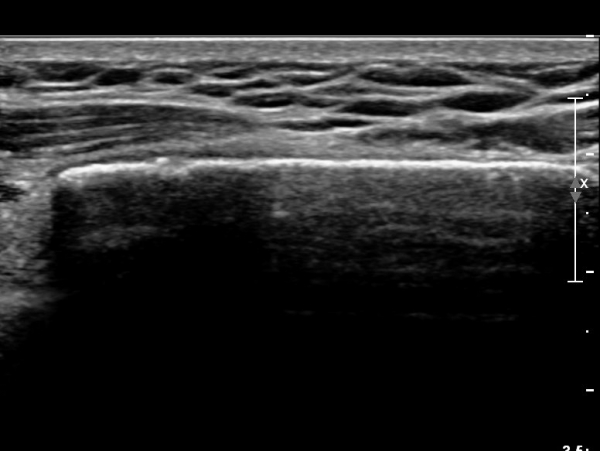

Á¶±Ý ´õ ¸»´ÜÀ¸·Î À̵¿ÇÏ´Ï Äá¾Ë»À ÇÇÁú°ñ ¿¬¼Ó¼º ¼Ò½ÇÀÌ °üÂûµÊ(»çÁö 3),